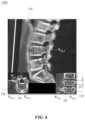

FIG.4 is a schematic diagram illustrating superimposition at a spinal segment location corresponding to an image superimposing step of the surgical navigation method ofFIG.2;

FIG.2 is a schematic flowchart illustrating asurgical navigation method100aaccording to another embodiment of the present disclosure.FIG.3 is a schematic diagram illustrating the guiding of asurgical instrument512 by using thesurgical navigation method100aofFIG.2.FIG.4 is a schematic diagram illustrating the superimposing at a spinal segment in an image superimposing step S16 of thesurgical navigation method100aofFIG.2.FIG.5 is a schematic diagram illustrating a superimposedviewing direction image130 of thesurgical navigation method100aofFIG.2.FIG.6 is a schematic diagram illustrating another superimposedviewing direction image130aof thesurgical navigation method100aofFIG.2.

In accordance with some embodiments of the present disclosure, the image superimposing step S16 includes superimposing thepart120P of the two-dimensionalspinal images120 along the at least one viewing angle direction D2 to form a superimposedviewing direction image130, where the superimposedviewing direction image130 presents at least one two-dimensional superimposed region (such as R2D_1, inFIG.4 and R2D_1, R2D_2and R2D_3inFIGS.5 and6) according to the at least one viewing angle direction D2, and the at least one two-dimensional superimposed region corresponds to the three-dimensional pedicle region R3D.

In accordance with embodiments of the present disclosure, the image superimposing step S16 is advantageous because high bone density regions appear white in a CT image, and because the pedicle surface density is high. Thus, the two-dimensional superimposed region corresponding to the three-dimensional pedicle region R3Dcan clearly identify the white pedicle contour in the picture. Additionally, different viewing angle directions D2, may generate different superimposedviewing direction images130 and corresponding two-dimensional superimposed regions, such as a coronal plane contour, a sagittal plane contour or a axial plane contour of pedicle. In accordance with some embodiments, the number of the viewing angle directions D2 is the same as that of the two-dimensional superimposed regions and the number may be plural, and the viewing angle directions D2 may include (but not limited to) a first viewing angle direction, a second viewing angle direction, and a third viewing angle direction. The two-dimensional superimposed regions may include (but not limited to) a first two-dimensional superimposed region R2D_1, a second two-dimensional superimposed region R2D_2, and a third two-dimensional superimposed region R2D_3. The superimposedviewing direction image130 may include (but not limited to) a superimposedcoronal plane132, a superimposedsagittal plane134, and a superimposedaxial plane136. The target point TP is close to the first two-dimensional superimposed region R2D_1, the second two-dimensional superimposed region R2D_2, and the third two-dimensional superimposed region R2D_3.

In accordance with some embodiments of the present disclosure, the superimposedcoronal plane132 has a two-dimensional coronal coordinate system, where the superimposedcoronal plane132 presents one or two first two-dimensional superimposed regions R2D_1according to the three-dimensional pedicle region R3Din the first viewing angle direction, and each first two-dimensional superimposed region R2D_1has a pedicle height H, a pedicle width W, and a closed contour. The closed contour is the coronal plane contour of pedicle.

In accordance with some embodiments of the present disclosure, the superimposedsagittal plane134 has a two-dimensional sagittal coordinate system, where the superimposedsagittal plane134 presents one second two-dimensional superimposed region R2D_2according to the three-dimensional pedicle region R3Din the second viewing angle direction, and the second two-dimensional superimposed region R2D_2has a pedicle length L, a pedicle height H, and a sagittal plane contour of pedicle.

In accordance with some embodiments of the present disclosure, the superimposedaxial plane136 has a two-dimensional abscissa system, where the superimposedaxial plane136 presents one or two third two-dimensional superimposed regions R2D_3according to the three-dimensional pedicle region R3Din the third viewing angle direction, and each third two-dimensional superimposed region R2D_3has the pedicle length L, the pedicle width W, and an axial plane contour of pedicle. After the image superimposing step S16, the pedicle contour of the spinal segment corresponding to the target point TP in the superimposedviewing direction image130 is the clearest.

As shown inFIG.4, in some embodiments, the viewing angle direction D2 of the superimposedcoronal plane132 may be the first viewing angle direction. In accordance with some embodiments, three-dimensionalspinal images110 generated by the CT scanning of one spinal segment along the cutting direction D1 corresponding to the first viewing angle direction include two-dimensionalspinal images120, and thepart120P of these two-dimensionalspinal images120 contains the three-dimensional pedicle region R3D.

The two-dimensionalspinal images120 are superimposed to form a superimposedcoronal plane132. The superimposedcoronal plane132 presents one or two first two-dimensional superimposed regions R2D_1according to the three-dimensional pedicle region R3Din the first viewing angle direction.